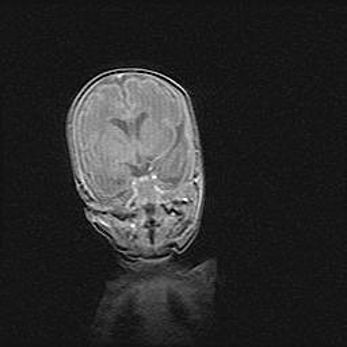

Церебральная ишемия II.

Возраст: 5 дней

Вес: 3400 г

Пол: женский

Окружность головы: 35 см

Срок гестации: 39 недель

Церебральная ишемия – это заболевание, характеризующееся недостаточностью (гипоксией) либо полным прекращением (аноксией) снабжения мозга кислородом по причине закупорки одного или нескольких сосудов. Это приводит к  что метаболическим расстройствам различной степени тяжести в тканях головного мозга, развитию коагуляционных некрозов и гибели нейронов.